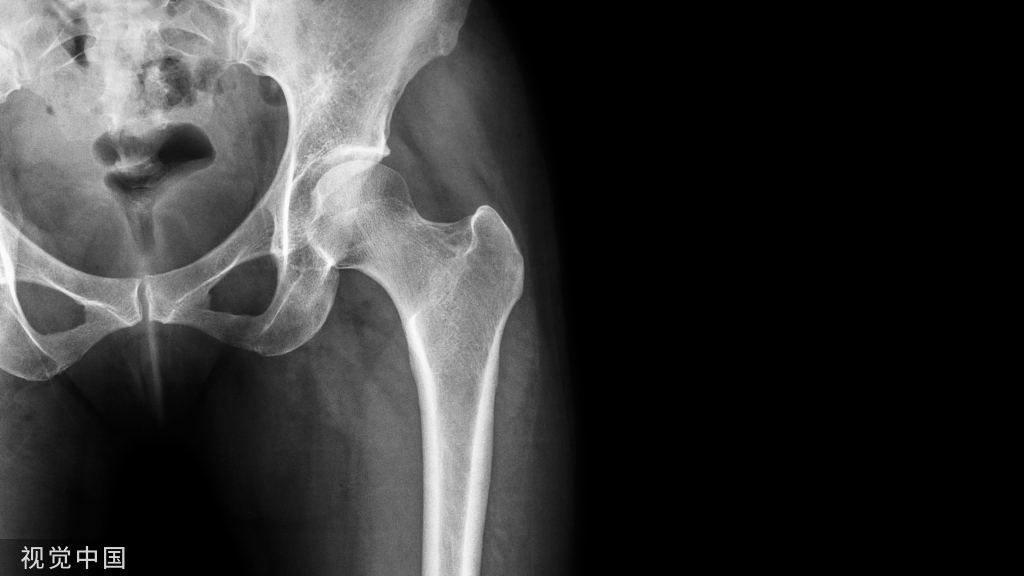

急诊就诊3天后门诊随访x线片显示锁骨中轴骨折倒v型移位